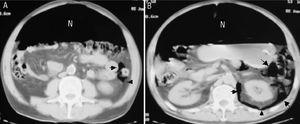

Un varón de 53 años acudió a un hospital comarcal por disnea de reposo, sudoración y dolorimiento en costado y hemiabdomen izquierdo de tres días de duración. Sus antecedentes personales incluían hipertensión arterial tratada con candesartán, tabaquismo y carcinoma epidermoide de lengua tratado con resección quirúrgica y posterior radioterapia y quimioterapia. La exploración puso de manifiesto una hipoventilación en el hemitórax izquierdo y un abdomen distendido, timpanizado, no doloroso y sin signos de irritación peritoneal. La presión arterial fue de 115/85 mmHg, el pulso de 123 latidos/minuto, la temperatura de 37,2 ºC. Los principales datos analíticos fueron: creatinina 3,9 mg/dl, urea 180 mg/dl, glucosa 193 mg/dl, leucocitos 24,4 miles/µl con un 95,7% de neutrófilos, hemoglobina 14,2 g/dl y gasometría arterial basal con pH 7,35, PaO2 64,7 mmHg, PaCO2 27,8 mmHg y bicarbonato 16 mmol/l. La radiografía de tórax mostró un neumotórax izquierdo y neumoperitoneo bilateral. Tras colocar un tubo de tórax anterosuperior, se realizó una tomografía computarizada toracoabdominal que reveló un neumotórax anterior izquierdo residual, aire mediastínico, neumoperitoneo masivo, aire pericólico libre intraperitoneal y retroneumoperitoneo (fig. 1). Seguidamente, se remitió al paciente a nuestro hospital para cirugía y cuidados postoperatorios. La intervención quirúrgica puso de manifiesto una diverticulosis sigmoidea y una perforación diverticular al espacio intraperitoneal y retroperitoneal. Se realizó una resección del sigma y colostomía tipo Hartmann. Inicialmente fue tratado con imipenen y teicoplanina, pero al sexto día de postoperatorio tuvo una sepsis grave por neumonía nosocomial derecha por Klebsiella pneumoniae y Streptococcus milleri que requirió ventilación mecánica y soporte vasoactivo con noradrenalina. El paciente falleció días más tarde a consecuencia de una hipoxia refractaria secundaria a un distrés respiratorio agudo.

Figura 1. Una tomografía computarizada abdominal con contraste evidencia neumoperitoneo masivo (N), aire pericólico izquierdo extraluminal e intraperitoneal (flechas) (A) y retroneumoperitoneo que delimita el riñón izquierdo (flechas) (B).